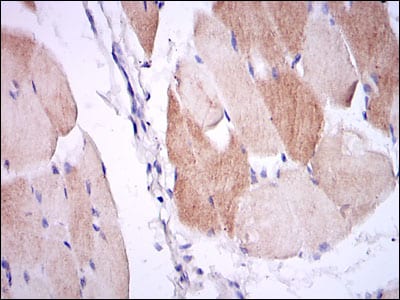

- Immunohistochemical analysis of paraffin-embedded human muscle tissues using IL1B mouse mAb with DAB staining.